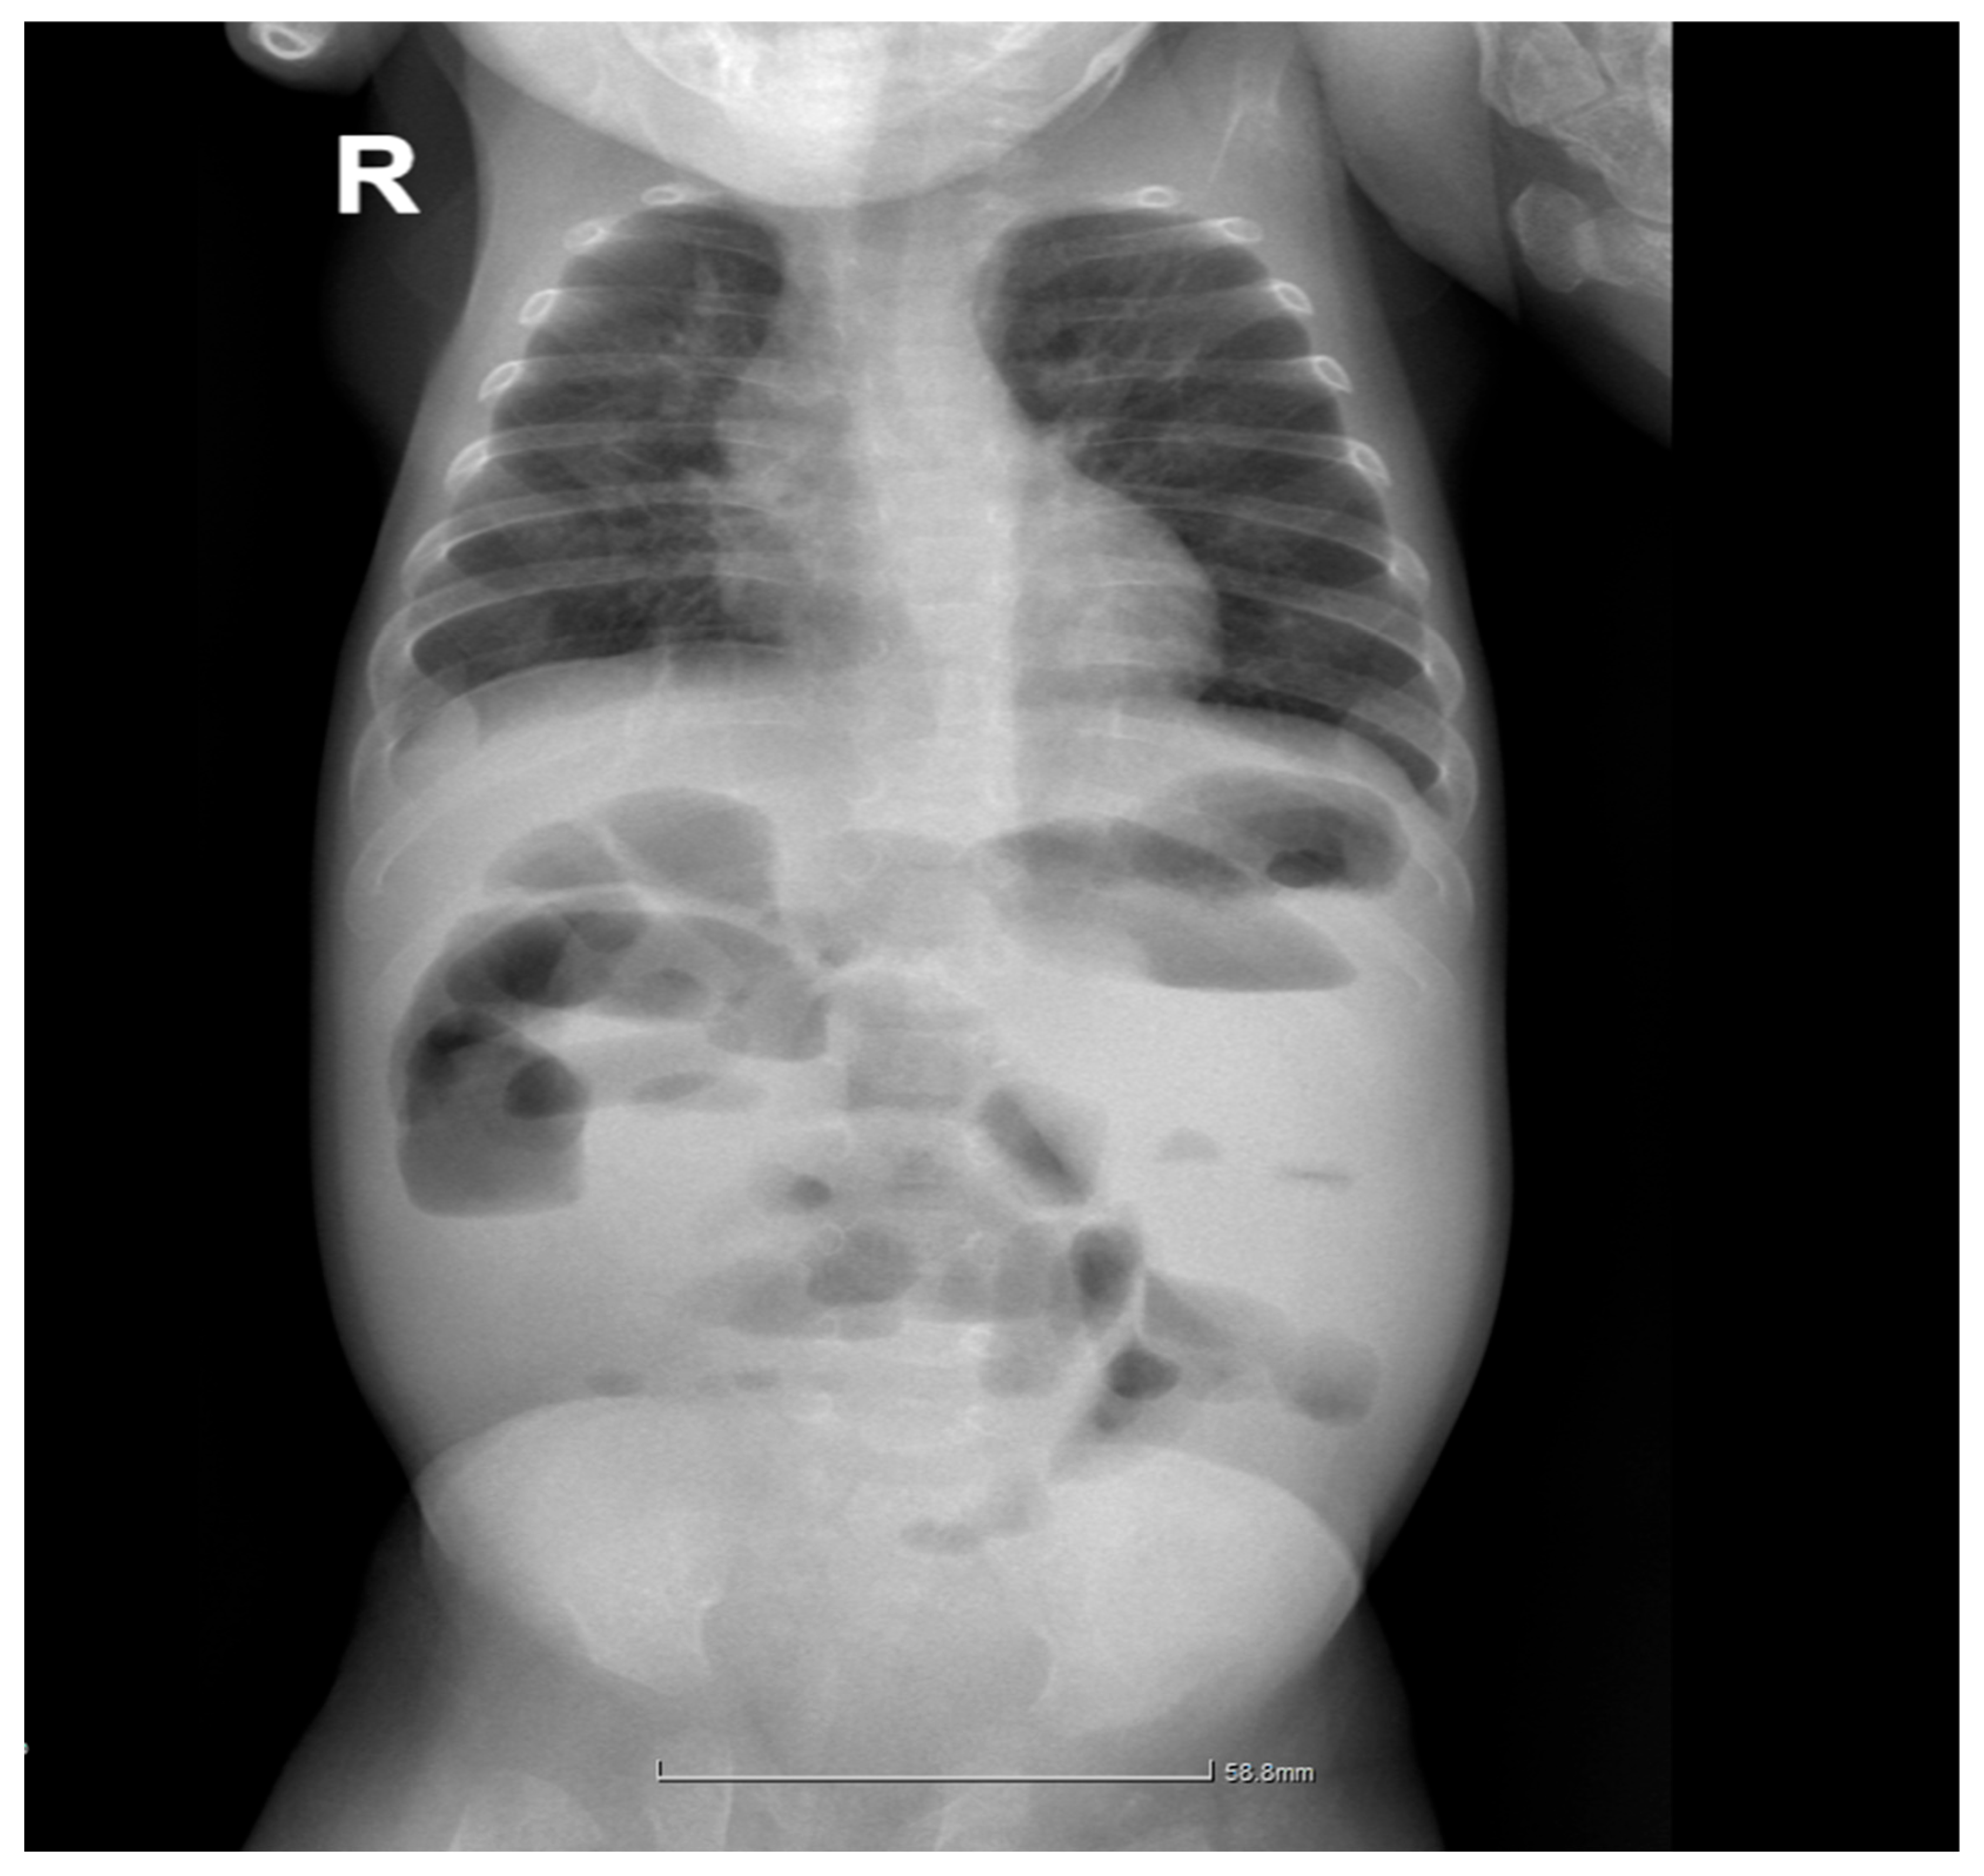

2.4. Gastrointestinal Complications and Diagnosis

| Day 12 | Intestinal obstruction suspected | Surgical consultation |